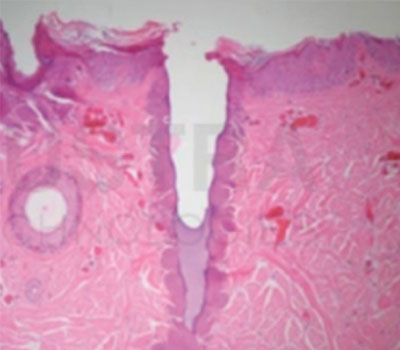

Cómo actúa el láser Tulio 1927 en la piel

Estimulación de colágeno y elastina: El depósito térmico focalizado desencadena respuesta reparativa con neocolagénesis y neoelastogénesis, mejorando firmeza y luminosidad progresivamente en las semanas posteriores.

Microcanales para drug delivery: Las microcolumnas dejan microcanales transitorios que facilitan la penetración de activos tópicos seleccionados, optimizando protocolos combinados en discromías y retexturización.